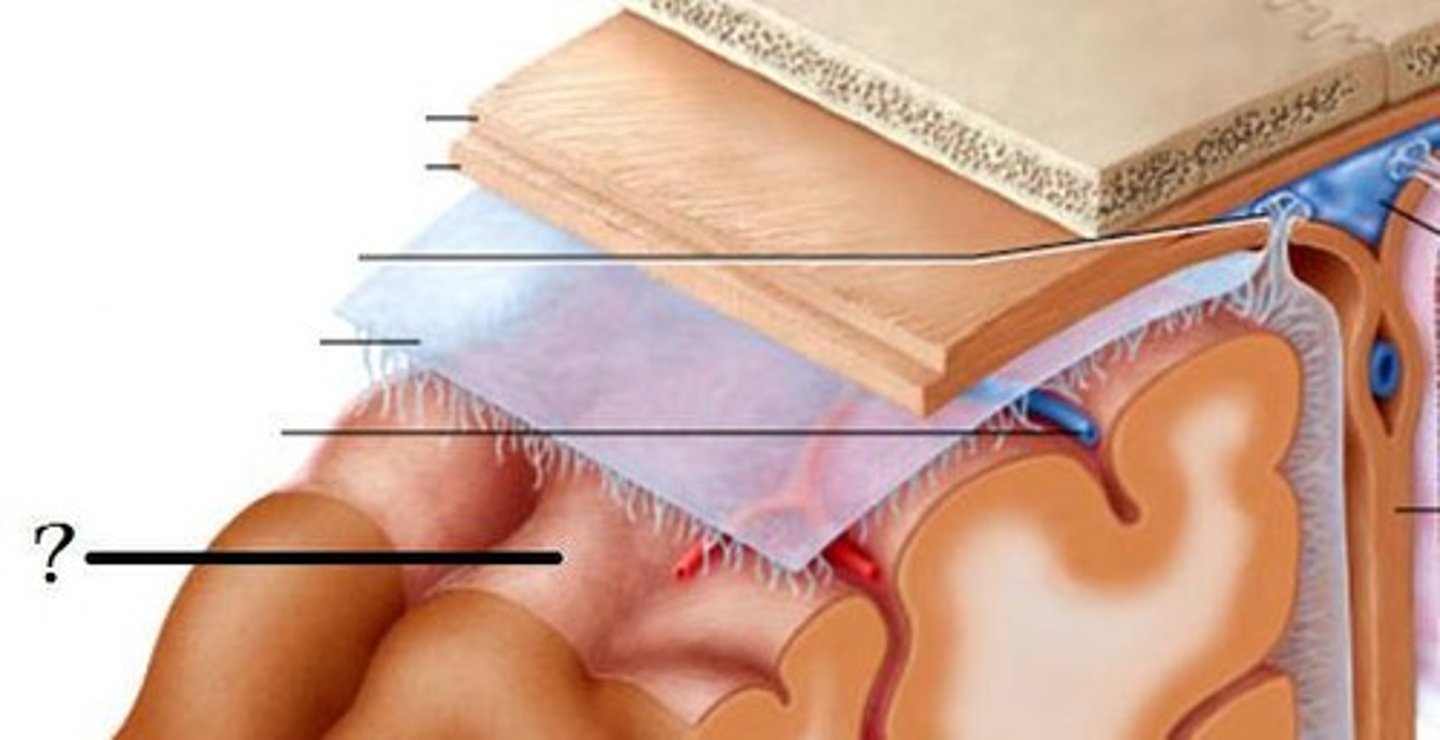

meninges

•Three connective tissue layers

•Separate and support soft tissue of brain

•Enclose and protect blood vessels supplying the brain

•Help contain and circulate cerebrospinal fluid

•From deep to superficial (PAD to protect the brain)

--Pia mater

--Arachnoid mater

--Dura mater

dura mater (brain)

thick, outermost layer of the meninges surrounding and protecting the brain and spinal cord

arachnoid mater (brain)

middle web-like layer of the meninges

pia mater (brain)

thin, delicate inner membrane of the meninges

spinal meninges

dura mater, arachnoid mater, pia mater (PAD to protect the spinal cord from deep to superficial)

dura mater (spinal cord)

thick, outermost layer of the meninges; 5 on image

arachnoid mater (spinal cord)

middle weblike layer of the meninges; 4 on image

pia mater (spinal cord)

thin, delicate inner membrane of the meninges; 3 on image

central canal of spinal cord

center of spinal cord which contains cerebrospinal fluid